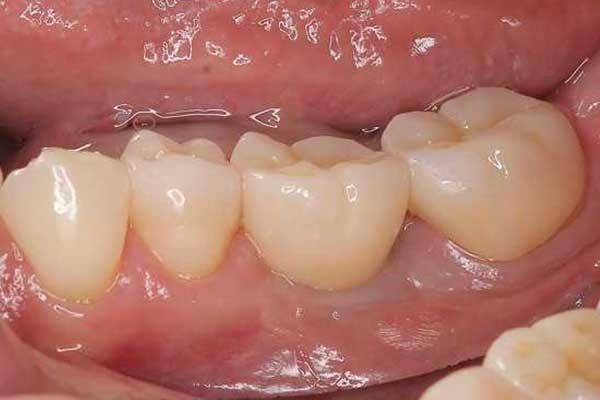

④ インプラント治療

治療中

治療後

年代・性別

70代・男性

お悩み

歯が折れた

治療内容

抜歯を行い、その後インプラント治療を行い新しく歯をつくりました。

治療期間・回数

8ヶ月

費用

約60万円(税込)

リスク・副作用

処置の際には様々な合併症が起こることがあります。